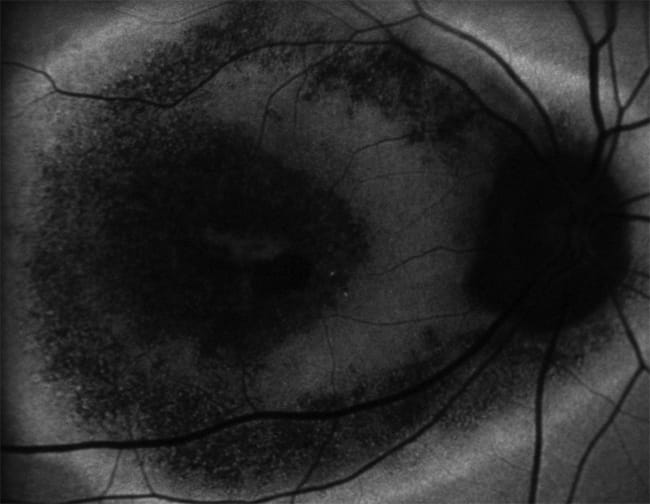

Another important recent innovation in FAF imaging is the adaptation of widefield fundus imaging systems, such as the Optos 200Tx, to perform autofluoresence imaging. Although it is an SLO system, the Optos FAF acquires images using green light, similar to flash-camera FAF. Recently, we have observed that peripheral AF abnormalities are quite common, present in over 70% of patients in a recent series at our institute. The clinical significance of these findings, however, is still uncertain. Peripheral FAF findings appear to be quite characteristic in some disorders, such as chronic Vogt-Koyanagi-Harada disease, which typically shows numerous nummular areas of decreased AF (Figure 7). The significance of peripheral AF abnormalities in patients with AMD will be explored further in the AREDS2 study.

Figure 7. Nummular areas of decreased AF in VKH disease.